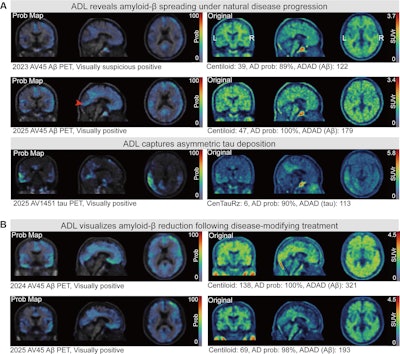

Adversarial decomposition learning (ADL) enables intuitive, longitudinal visualization of disease progression and treatment response, supporting clinician–artificial intelligence collaboration. (A) Images in a 48-year-old female patient who presented with mild cognitive impairment. The ADL probability maps highlighted occipital-temporal amyloid β (Aβ) spread and focal left-temporal tau pathologic abnormalities. An area of increased occipital AV45 uptake is shown (arrowhead). (B) Images in a 51-year-old male who presented with memory decline. For each image grid, the left side is the decoupler-output AD pathologic probability map, the upper right side is the original Aβ/tau PET image, and the lower right side is the image after AD component removal by the decoupler.Adversarial decomposition learning (ADL) enables intuitive, longitudinal visualization of disease progression and treatment response, supporting clinician–artificial intelligence collaboration. (A) Images in a 48-year-old female patient who presented with mild cognitive impairment. The ADL probability maps highlighted occipital-temporal amyloid β (Aβ) spread and focal left-temporal tau pathologic abnormalities. An area of increased occipital AV45 uptake is shown (arrowhead). (B) Images in a 51-year-old male who presented with memory decline. For each image grid, the left side is the decoupler-output AD pathologic probability map, the upper right side is the original Aβ/tau PET image, and the lower right side is the image after AD component removal by the decoupler.Image and caption courtesy of RSNA.